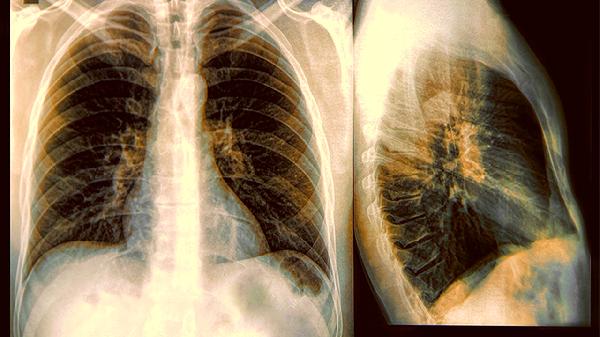

低劑量CT檢查的輻射量相當於坐20次飛機,對高危家庭而言利大於弊。建議長期接觸二手煙的青少年,每年做一次肺功能吹氣檢查,這項無創檢測能發現早期氣道病變。